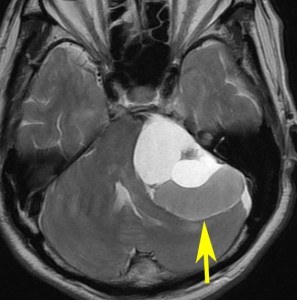

腫瘍が嚢胞性拡大で大きくなって,腫瘍内出血して,閉塞性水頭症になって意識障害を生じた患者さんです。このような事態になると臨時手術で腫瘍を摘出します。

大きなのう胞性聴神経腫瘍です。いくつかの袋が重なって腫瘍を形成しています。橋や延髄(脳幹部)が変形して,第4脳室がつぶれて閉塞しています。袋の周りが白く線状に造影されているのですが,この袋の壁だけに腫瘍細胞がありますから,これを剥がすように摘出します。顔面神経が薄くなって袋の壁にくっついているのですが,袋を破ってくしゃくしゃにすると顔面神経の位置が変わってしまって,顔面神経を損傷することがあるので要注意です。のう胞性聴神経腫瘍の方が顔面神経麻痺の後遺症の頻度が高いという報告もあるくらいです。この患者さんは迷走神経と舌咽神経の圧迫も強くて,ご飯を飲み込むことが難しくなっていました(嚥下障害)。

また,この患者さんは急に容態が悪くなって意識障害となりました。何故なら腫瘍の内部で出血したからです(黄色の矢印の部分)。第4脳室が詰まって閉塞性水頭症になって側脳室が拡大しています(右の画像)。